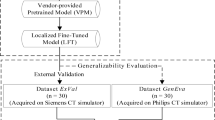

A schematic workflow of this study is presented in Fig. 1. After auto-segmentation, the assessment was divided into three parts. First, the accuracy of auto-segmentation was evaluated based on geometric metrics. Second, we reoptimized the plan based on the auto-segmented OARs and compared it with the original treatment plan to evaluate the dosimetric differences. Third, we explored the correlation between the geometric metrics and dosimetric differences.